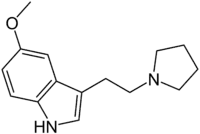

| 5-MeO-pyr-T | artificial | 5-OCH3 | (CH2)4 | 5-Methoxy-3-[2-(pyrrolidin-1-yl)ethyl]-1H-indole | 3949-14-2 | |